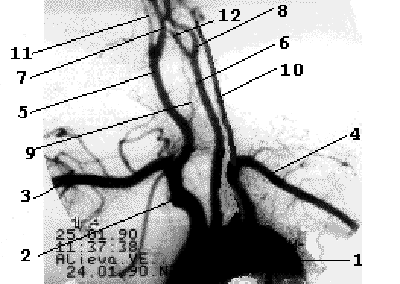

От дуги аорты отходят три основных артериальных ствола - слева общая сонная и подключичная артерии, справа - короткий брахиоцефальный ствол, который делится на правую подключичную и правую общую сонную артерии. Обе позвоночные артерии отходят от соименных подключичных артерий, являясь границей первого и второго сегментов ПКА. Общая сонная артерия у верхнего края щитовидного хряща делится на наружную сонную артерию и внутреннюю сонную артерию (рис. 1.3).

Рис 1.3

Рентгеноанатомия брахиоцефальных ветвей дуги аорты.

1- дуга аорты, 2- брахиоцефальный ствол, 3- правая ПКА, 4- левая ПКА, 5- правая ОСА, 6- левая ОСА, 7- правая ВСА, 8- левая ВСА, 9- правая ПА, 10- левая ПА, 11- правая НСА, 12- левая НСА.